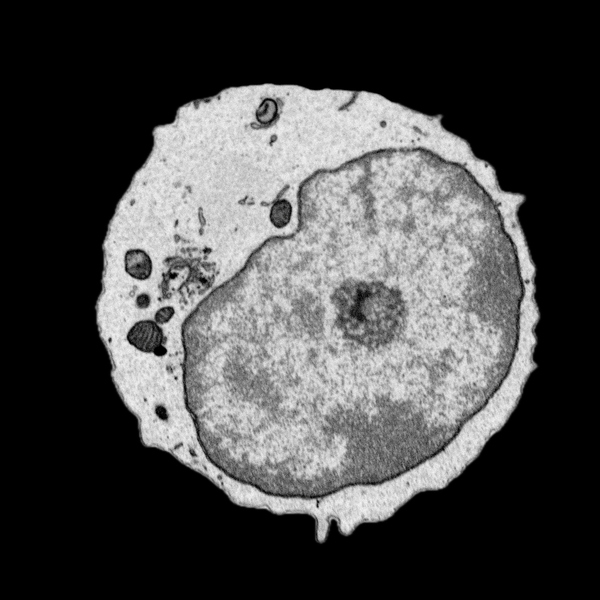

On Monday 25 November, Ionut Sebastian Mihai, Department of Molecular Biology, defended his thesis entitled “A systems biology single cell approach for querying the differentiation of immune system and antiviral response”. The faculty opponent was Dr. Karine Chemin, from Karolinska Institutet.